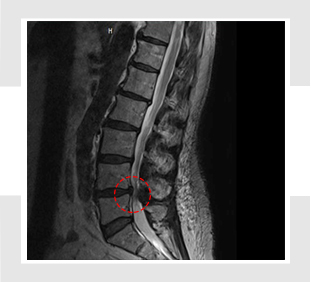

오늘 글에서는 척추관 협착증 증상 치료방법에 대해서 알아보도록 하겠어요. 척추관 협착증은 퇴행성 디스크와 아울러 전형적인 퇴행성 척추질환입니다. 척추의 퇴행이 오래 진행되어 인대가 두꺼워지고 붓게 된다면 신경구멍이 좁아지며 척추관 협착증이 유발되요.

척추 관절과 인대가 변경되고 두꺼워져 척추 신경을 조이면 신경의 혈액순환이 모자라게 되어 생겨해요. 선천적으로 요추관의 정도가 정상보다 작게 만들어지는 경우로, 대개는 35세가 넘어 뼈와 인대의 변환가 연거푸해서 증상이 형성되나 20세 전후의 아주 젊은 나이에도 띄엄띄엄 발견되요.

최고 많이 보이는 원인으로 척추 퇴행성 골관절염이 생김에 따라 허리 관절의 정도가 많아지고 인대도 두꺼워지는 더불어 가시 같은 뼈가 자라나 신경 길을 좁아지게 해요.

척추관 협착증은 척추 관절과 주변 조직의 변화로 인해 나타나는 질환입니다. 이 질환의 원인은 자연적인 단계인 노화로 인한 척추 관절 연골 파괴와 뼈 형태적 전환, 디스크의 노화나 손상, 척추 골절, 척추 관절 염증, 그리고 선천적인 이상 등 각가지 요소들이 복합적으로 활동하여 생겨날수 있고요.